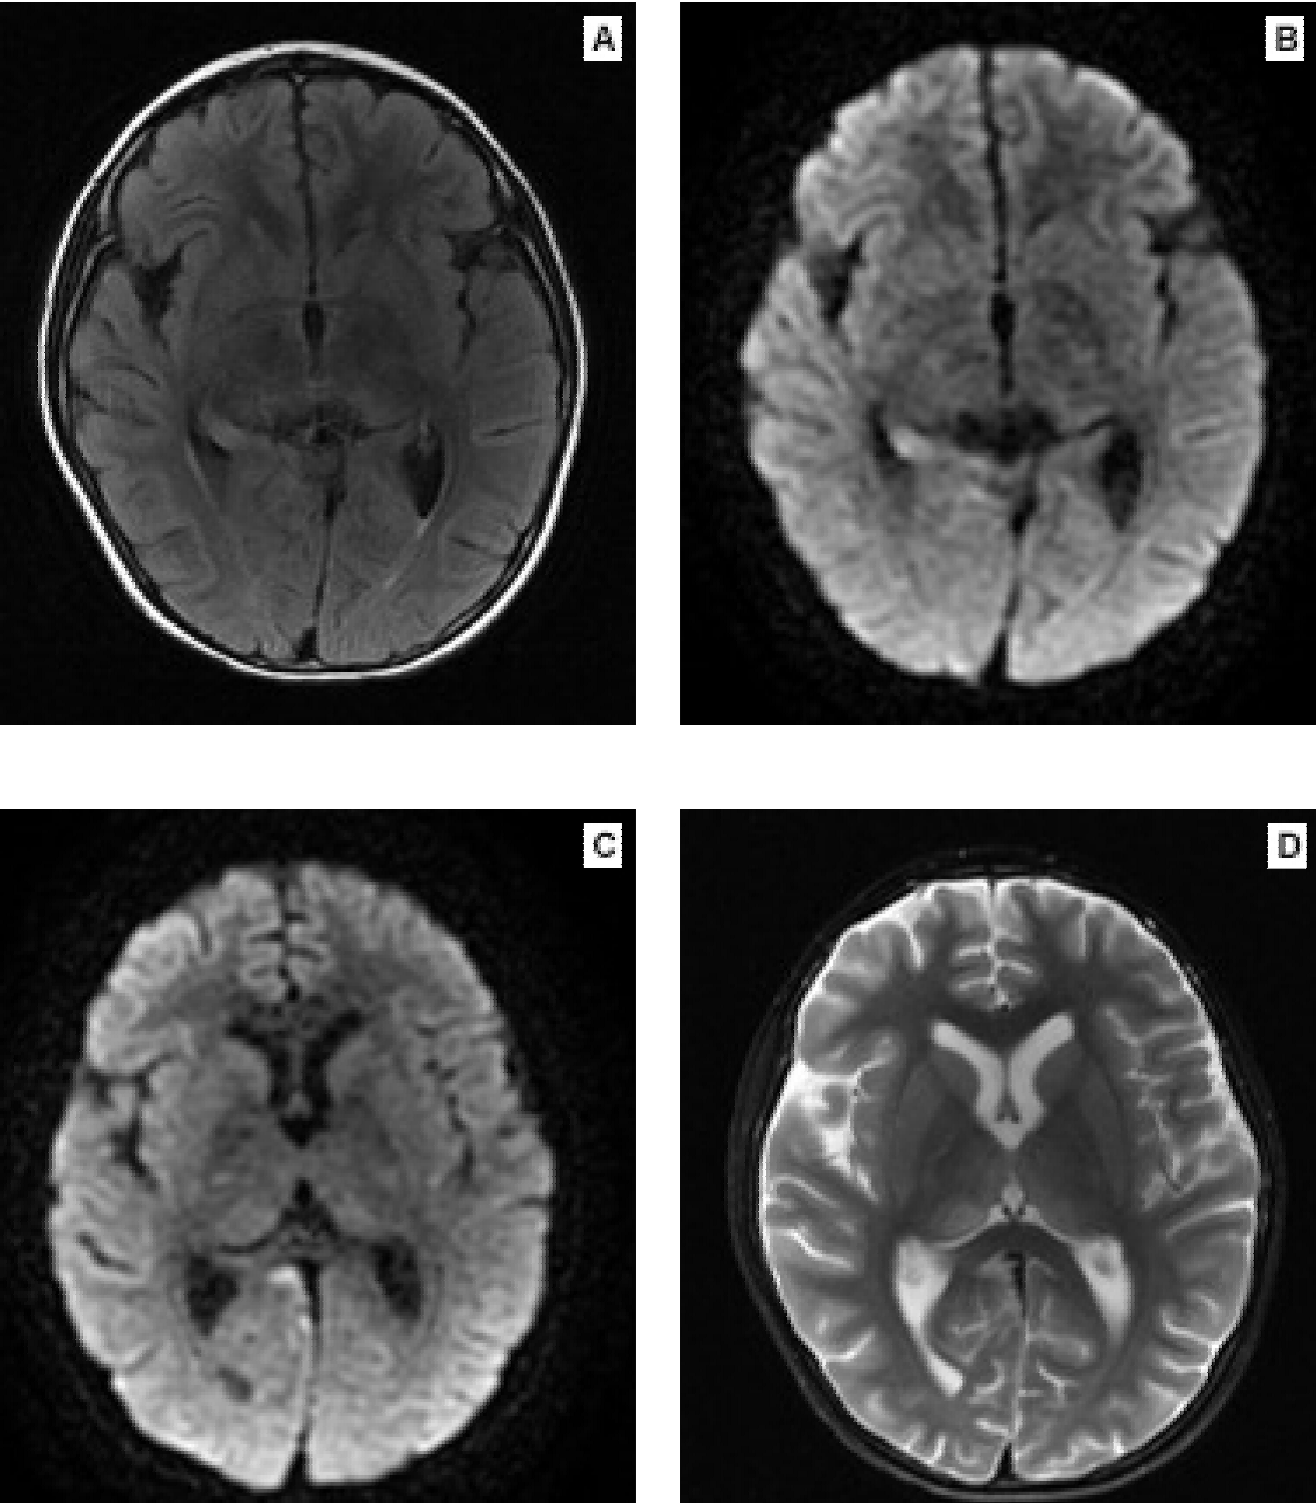

La encefalopatía límbica se caracteriza por cuadro súbito asociado a confusión, déficit de memoria, cambios de humor y, a menudo, convulsiones. El desarrollo subagudo de pérdida de memoria a corto plazo se considera el sello distintivo de este trastorno;7 los criterios diagnósticos se describen en el Cuadro 4 y los hallazgos por imagen de resonancia magnética cerebral se aprecian en la Figura 1.

Figura 1. Imágenes de resonancia magnética cerebral. A) Corte coronal secuencia FLAIR, con hiperintensidad en región mesial derecha. B y C) Corte axial difusión, con restricción asociada en la misma zona y extensión a región cingular. D) Corte axial T2 en el que se observa hiperintesidad con edema vasogénico a nivel pulvinar y dorsomedial del támalo progresivo. Cortesía: Servicio de Radiología del Hospital Infantil Universitario de San José, Bogotá, Colombia.